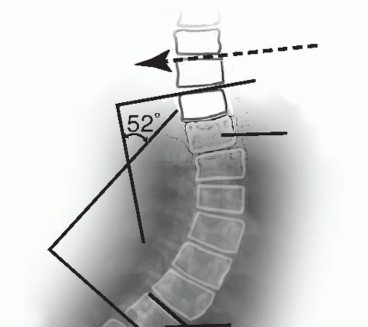

Standing posteroanterior (PA) radiographs on 36-inch cassettes characterize the spinal deformity by The magnitude of primary and compensatory curves, by the Cobb method (FIG 3)

FIG 3 • The Cobb method is used to measure the coronal deformity. Vertebral endplates (or the margins of pedicles) are used to extend lines as depicted for each of the curves involved. Lines orthogonal to these are then compared to determine the scoliosis angle. Vertebrae are typically selected to maximize the Cobb angle on each measurement.

FIG 3 • The Cobb method is used to measure the coronal deformity. Vertebral endplates (or the margins of pedicles) are used to extend lines as depicted for each of the curves involved. Lines orthogonal to these are then compared to determine the scoliosis angle. Vertebrae are typically selected to maximize the Cobb angle on each measurement.